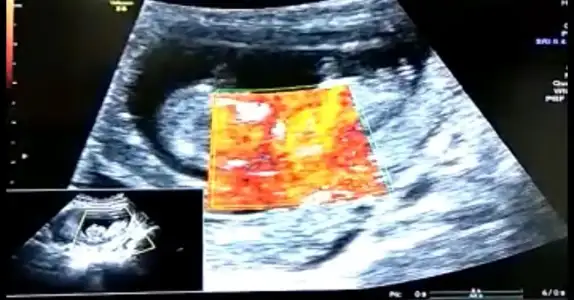

👫 11 yada 12 yada 13 hafta Nub usg nizi konumuza paylaşın

Arkadaşlar tahmin var mı? Özellikle ikra meyra :) Rabbim hayırlısını nasip etsin inşallah. 11+5